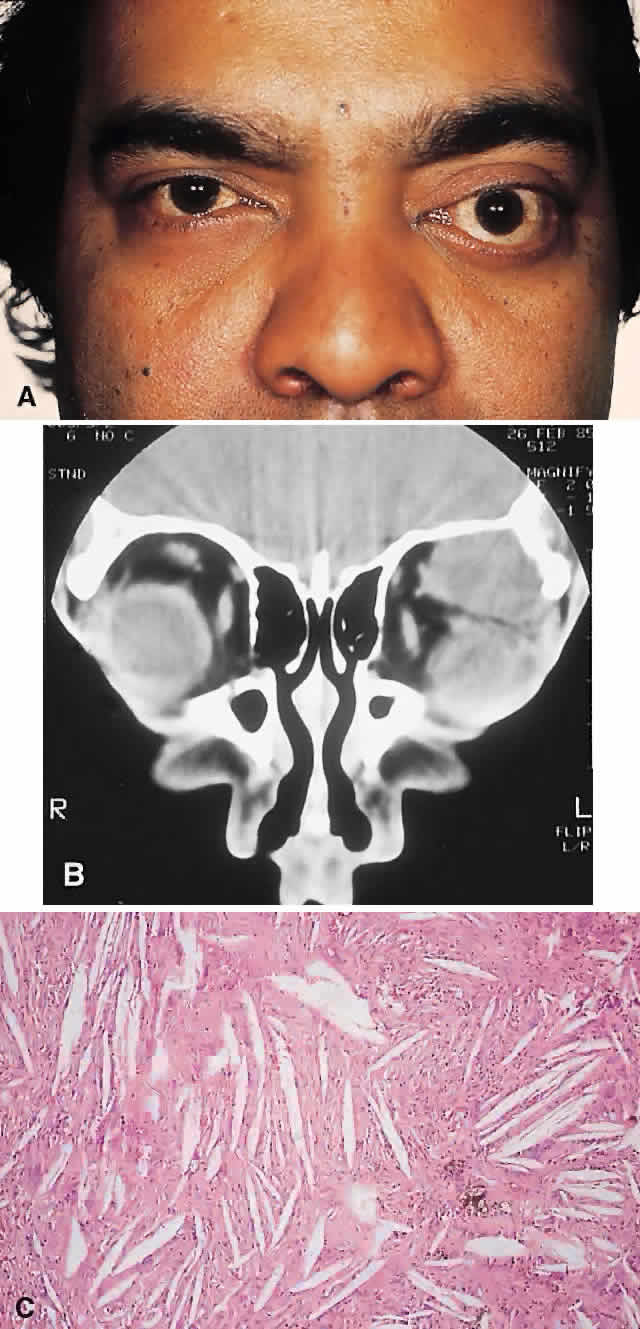

PRESENTATION. A superolateral mass effect encompassing weeks to years is the typical mode of presentation. This leads to inferior globe displacement, proptosis, and diplopia in upgaze (Fig. 5). There may be associated headache or pain; one third of patients recall a prior trauma.70,71

Fig. 5. A 41-year-old man had a 2-year history of left proptosis and headaches. A. Examination found 6 mm of proptosis with 4 mm of inferior ocular displacement. B. CT showed an osteolytic mass arising from the superolateral frontal bone and extending into the orbit. C. Histologically, a classic picture of cholesterol granuloma was apparent, with numerous cholesterol clefts surrounded by granulomatous inflammation containing foreign body giant cells (hematoxylineosin, × 20).

IMAGING. The granuloma arises in the diploë of the frontal bone, causing expansion and eventually erosion of the inner and outer tables. CT reveals it to be osteolytic, with a density equivalent to brain, and occasional intralesional bone fragments.72 Mature lesions display high T1 and T2 signal intensities on MRI.73,74 The most commonly evoked differentials in this setting are dermoid cysts and lacrimal gland carcinomas.

HISTOPATHOLOGY. These cysts usually contain yellow-brown viscous material with friable tissue and porous bone at the periphery. Histologically, the principal feature is the dominance of cholesterol clefts surrounded by granulomatous inflammation with conspicuous foreign body giant cells. A variable fibrous stroma is present and usually contains extensive blood-derived debris in the form of extracellular and intracellular hemosiderin as well as more recent hemorrhage.70,75